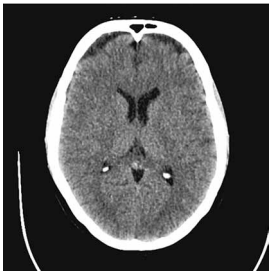

Paciente de 54 anos de idade, com história de febre,

cefaleia intensa, vômitos e rebaixamento do nível de

consciência há 24h. Glasgow 11; FC: 118 bpm; PA:

86 × 54 mmHg; Tax: 38,6 ºC; petéquias em tronco.

SpO2: 96% em O2. Realizou-se a tomografia de crânio

a seguir: